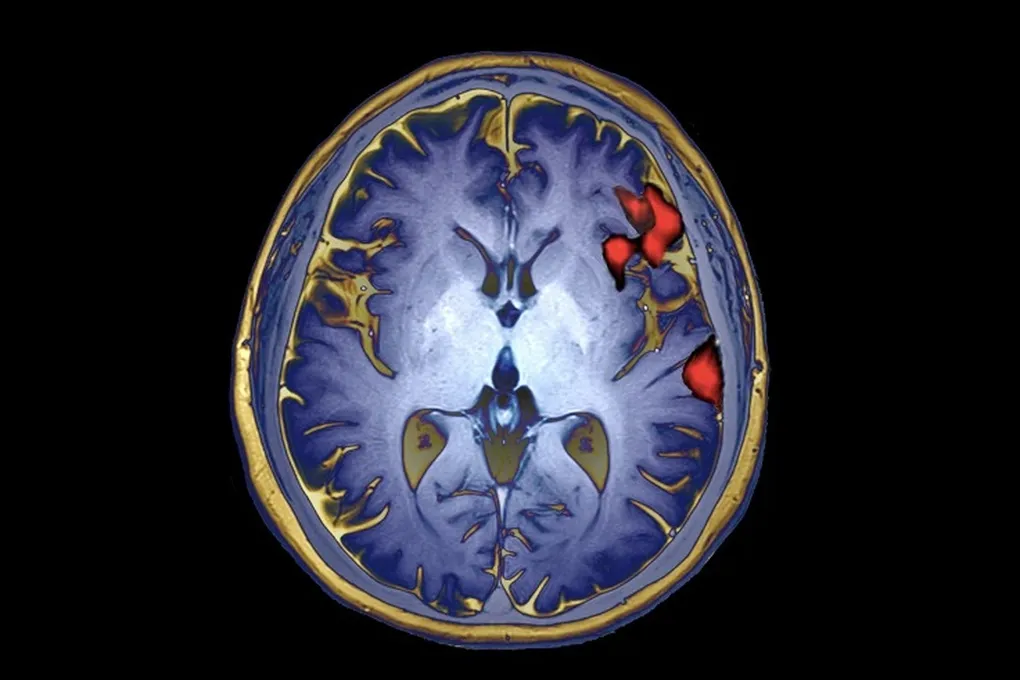

История этого открытия началась с человека, которого в исследовании называют Панчо. После инсульта в 20 лет он оказался в ловушке собственного тела: практически полностью парализованным и лишенным речи. Десять лет спустя он стал героем смелого эксперимента команды нейрохирурга Эдварда Чанга. В его мозг имплантировали электроды, которые считывают активность нейронов. А дальше в дело вступила умная система, которая научилась переводить эти тихие электрические «мысли» в громкие и четкие слова.